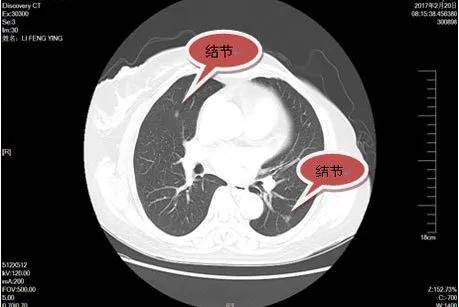

肺部筛查

肺癌在恶心肿瘤排行一直居高不下,比第二名的胃癌总数足足多了一倍。在大多数体检套餐中X光检测肺癌分辨率低,如果胸部X光片检查诊断是肺癌,临床常常就已经到晚期了。

建议在体检使用低剂量CT进行检测,低剂量肺部CT可以判断肺部疾病有肺结核、支气管扩张、肺炎、肺部肿瘤等,肺部1-4毫米的结节都能发现。建议50岁以上的中老年人或者有肺癌家族史的人把体检中的X光片换成CT。